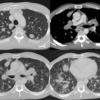

Lymphoma CT

Date: 04/25/2009

Views: 2980